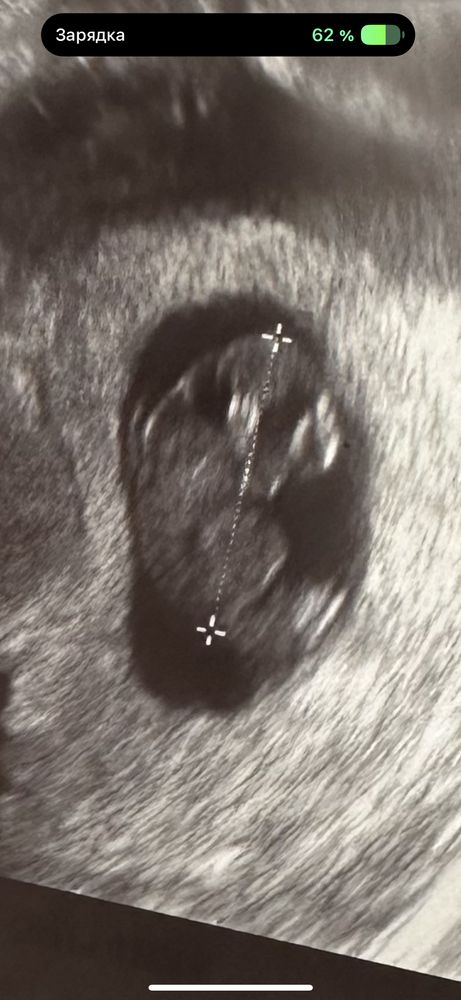

в пятницу еще все было хорошо, ктр 21 мм, чсс 149, через 5 дней ктр 27 мм, а сердцебиения уже нет. Зато есть большой отёк мягких тканей (двойной контур) и гигрома шеи.

Мне кажется или в пятницу уже было увеличено воротниковое пространство? Вообще из-за чего это бывает?

Если я правильно вижу то твп большое, хотя многие говорят на него не смотрят на таком сроке, но смотрят нормальные врачи всегда, пгд к сожалению не на всю генетику делают. Очень жаль что так получилось. Держитесь